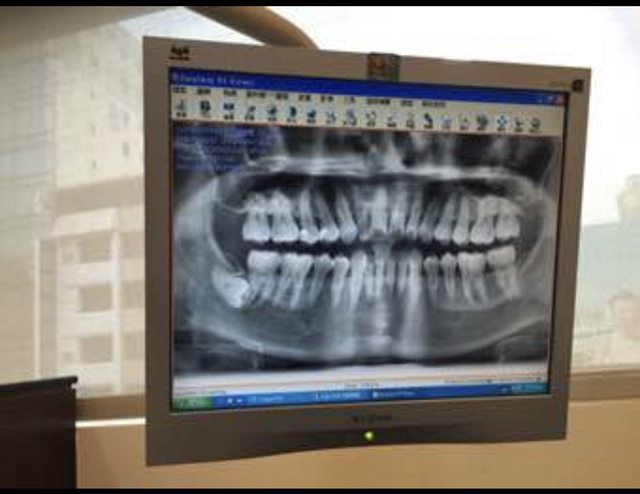

去看醫生照X光他傻眼

https://i.imgur.com/82aIEpj.jpg

他說你的旁邊有一顆完整成長

橫躺的智齒噎

你都不會痛嗎